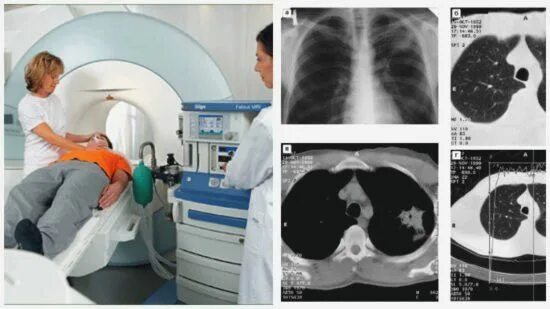

Кт сколько по времени длится процедура легких